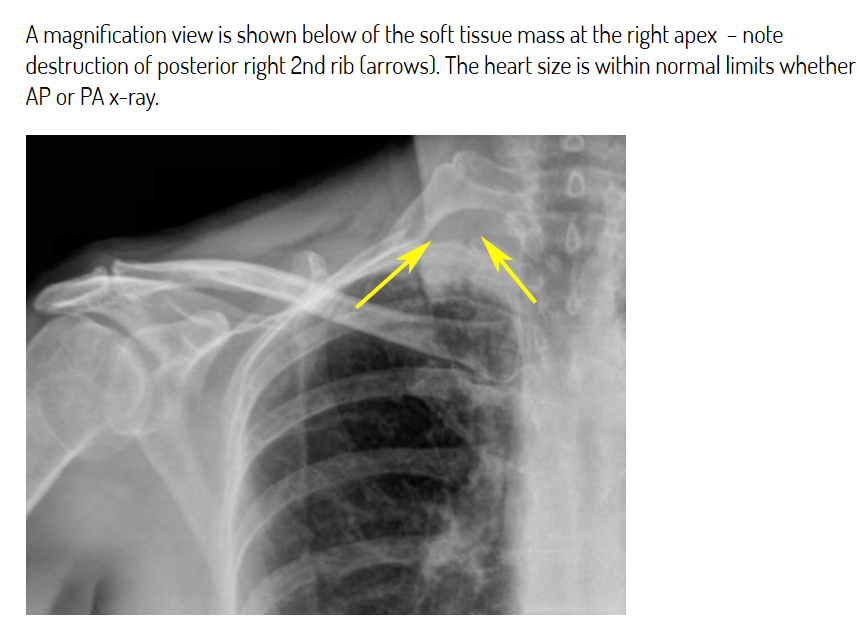

What is shown here? What is the diagnosis?

Pancoast tumour - can cause rib destruction.

Name 5 features of Pancoast syndrome.

Pancoast tumour invading surrounding structures –> symptoms called Pancoast syndrome

Invasion starts w/ brachial plexus –> shoulder and arm pain. There may be compression of the spinal cord which occurs in 10-25% of people with Pancoast.